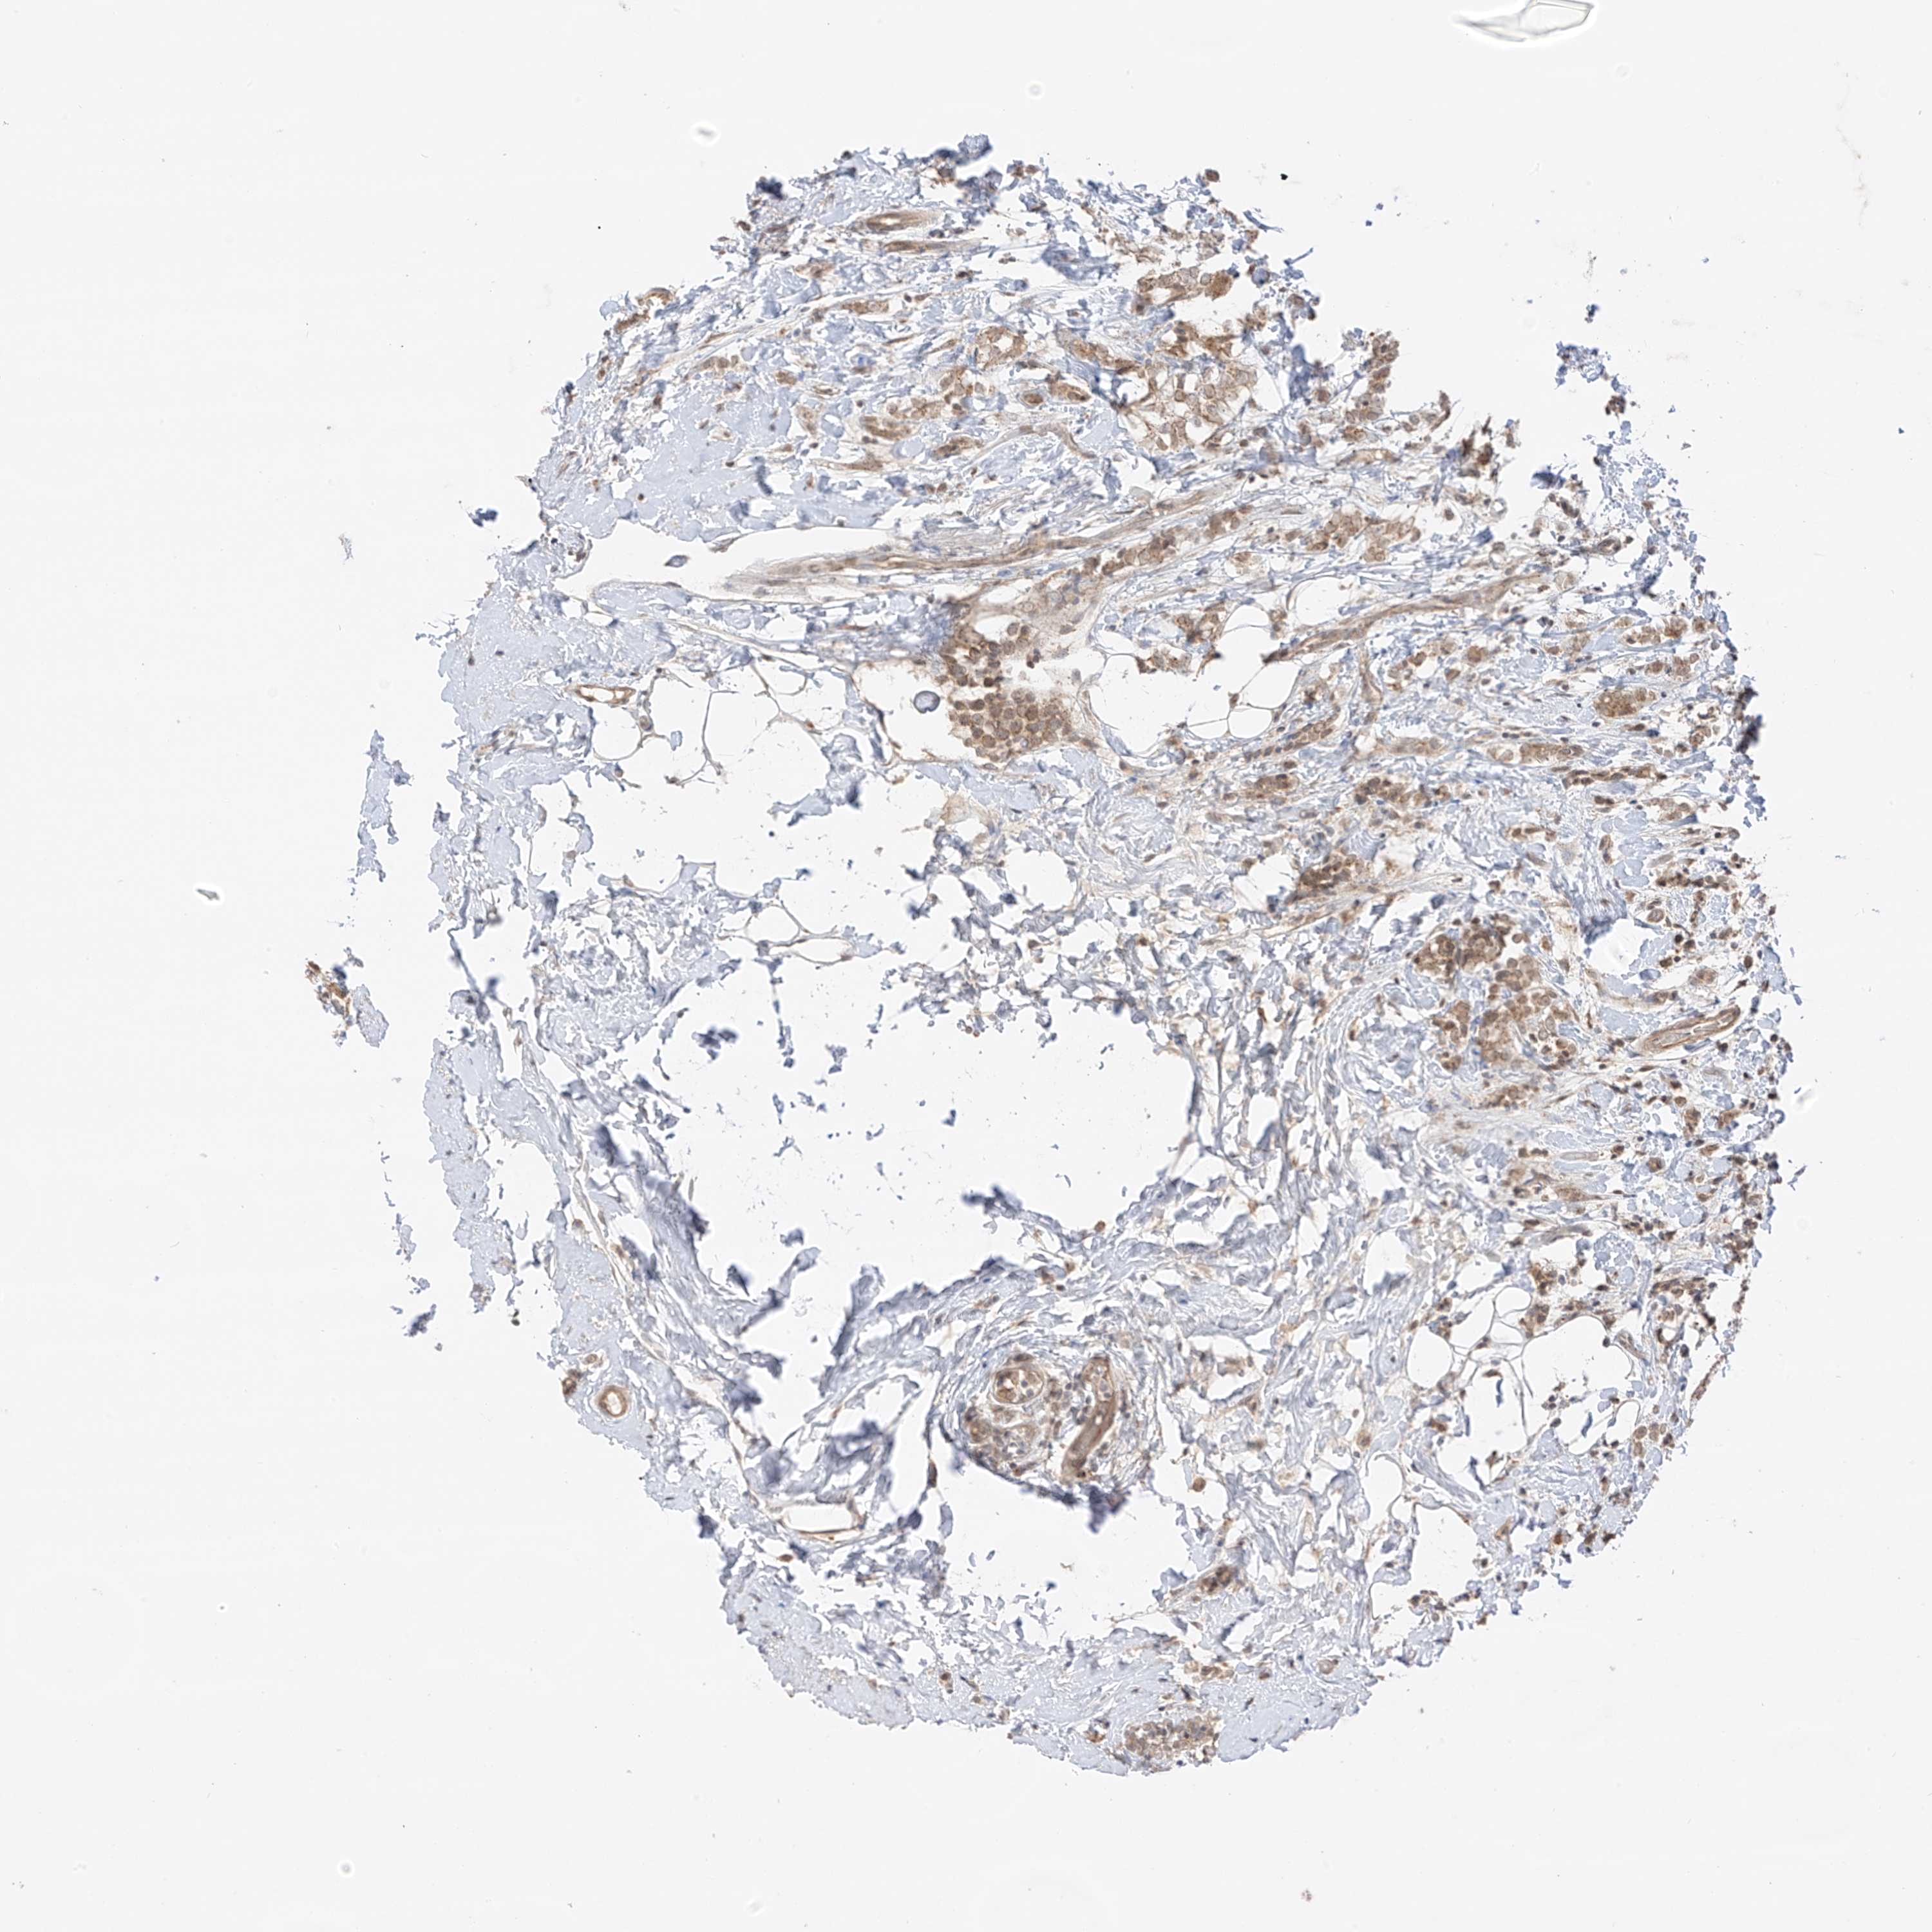

CANCER BREAST CANCER Show tissue menu

BRCA TCGA BRCA VALIDATION PROTEIN EXPRESSION